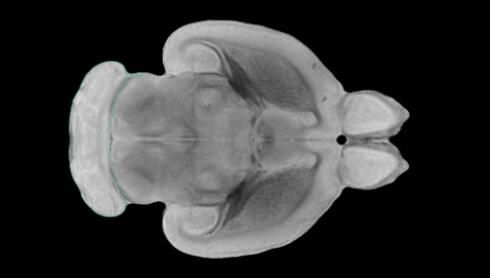

近日,一項(xiàng)刊登在國際雜志Nature上的研究報(bào)告中,來自劍橋大學(xué)的科學(xué)家們通過研究揭示了隨著年齡增長大腦僵硬程度的增加導(dǎo)致大腦干細(xì)胞功能異常的分子機(jī)制,同時(shí)研究者還開發(fā)出了一種新方法能將老化的干細(xì)胞逆轉(zhuǎn)回年齡健康狀態(tài);相關(guān)研究結(jié)果有望幫助研究人員理解機(jī)體大腦的老化過程以及如何開發(fā)治療年齡相關(guān)大腦疾病的新型療法。

隨著機(jī)體年齡增加,肌肉和關(guān)節(jié)都會(huì)變得僵硬,這就會(huì)使得日?;顒?dòng)變得更加困難,本文研究表明,我們的大腦也是如此,與年齡相關(guān)的大腦僵硬對大腦干細(xì)胞的功能或許有著重要影響。文章中,研究人員對年輕和老化大鼠的大腦進(jìn)行研究闡明了年齡相關(guān)大腦僵硬對少突膠質(zhì)前體細(xì)胞(OPCs,oligodendrocyte progenitor cells)功能的影響。OPCs是一類對維持正常大腦功能非常重要的大腦干細(xì)胞,其對于髓磷脂的再生也非常重要,髓磷脂是神經(jīng)組織周圍的脂肪鞘,在多發(fā)性硬化癥中髓磷脂的再生常常會(huì)被損傷,機(jī)體老化對這些細(xì)胞的影響常常會(huì)誘發(fā)多發(fā)性硬化癥的發(fā)生,這些細(xì)胞的功能在老化的健康人群中同樣會(huì)下降。

為了確定老化OPCs的功能缺失是否可以被逆轉(zhuǎn),研究人員將來自老化大鼠機(jī)體的老化OPCs轉(zhuǎn)移到了年輕大鼠柔軟的海綿狀大腦組織中去,值得注意的是,這些老化的大腦細(xì)胞能夠重新恢復(fù)活力,其行為非常像年輕更加強(qiáng)壯的細(xì)胞。這項(xiàng)研究中,研究人員在實(shí)驗(yàn)室中開發(fā)出了具有可變僵硬程度的新型材料,并在受控環(huán)境下研究這些材料的生長及其對大鼠大腦干細(xì)胞的影響,這些材料能被工程化改造具有和年齡或老化大腦相似的柔軟程度。

為了深入理解大腦組織柔軟和僵硬影響細(xì)胞行為的分子機(jī)制,研究人員對細(xì)胞表面一種名為Piezo1的蛋白質(zhì)進(jìn)行了分析,該蛋白質(zhì)能“告知”細(xì)胞其周圍的環(huán)境為柔軟或僵硬。研究者Kevin Chalut說道,我們發(fā)現(xiàn),當(dāng)在僵硬材料上促進(jìn)年輕具有功能性的大鼠干細(xì)胞時(shí),這些細(xì)胞就會(huì)表現(xiàn)出功能異常,并失去其再生的能力,實(shí)際上其行為與老化細(xì)胞相似。當(dāng)將老化的大腦細(xì)胞在柔軟材料上生長時(shí),其功能就會(huì)表現(xiàn)得像年輕細(xì)胞一樣,換句話說,其能夠重新恢復(fù)年輕的活力。

當(dāng)研究者從老化大腦干細(xì)胞的表面剔除Piezo1蛋白后,他們就能夠誘騙細(xì)胞感知柔軟的周圍環(huán)境,甚至當(dāng)將細(xì)胞在僵硬材料上生長時(shí)也是如此。此外,當(dāng)在老化大鼠大腦中剔除OPCs上的Piezo1時(shí),就會(huì)促進(jìn)細(xì)胞變得年輕并再次承擔(dān)正常的再生功能。研究者Susan Kohlhaas表示,多發(fā)性硬化癥是一種痛苦讓患者致殘的疾病,隨著時(shí)間推移,我們迫切需要開發(fā)出減緩并抑制患者殘疾的新型療法。這項(xiàng)研究中,研究人員闡明了大腦干細(xì)胞老化的分子機(jī)制,以及如何通過逆轉(zhuǎn)該過程來實(shí)現(xiàn)恢復(fù)大腦干細(xì)胞活力,后期研究人員將會(huì)基于本文研究開發(fā)出新型療法來治療多種與老化和多發(fā)性硬化癥相關(guān)的疾病,包括如何潛在恢復(fù)大腦失去的功能等。